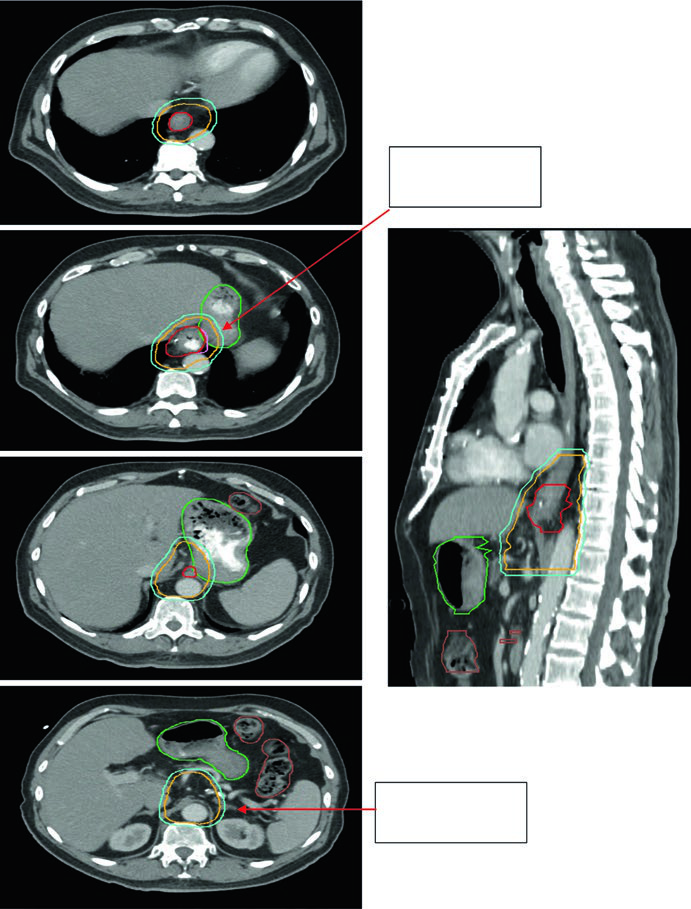

Caso 3: Adenocarcinoma de JGE — 75 anos, uT3N0

Paciente de 75 anos com adenocarcinoma de junção gastroesofágica uT3N0. Os contornos demonstram extensão do CTV para o estômago proximal, com cobertura até o eixo celíaco. Volumes delineados: estômago (verde escuro), intestino grosso (marrom), GTV esofágico (vermelho), CTV (laranja), PTV 50,4 Gy (ciano). A inclusão do eixo celíaco é mandatória para tumores distais e de JGE.